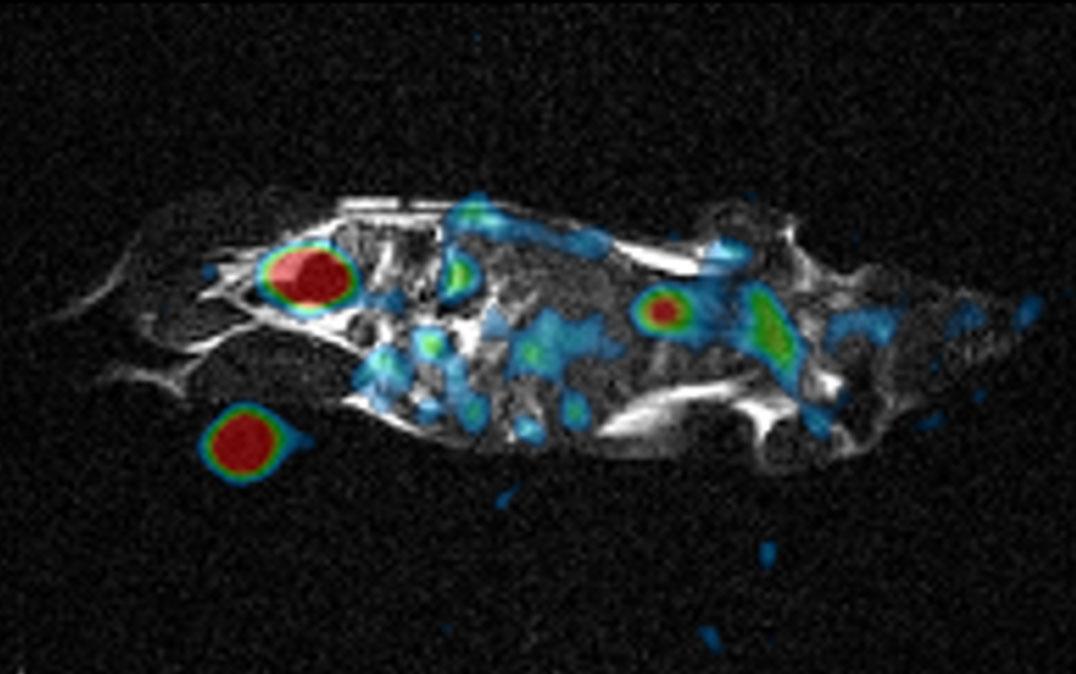

The research team tested the system with a saline "phantom" and an anesthetized mouse. Even though the resulting signal was much lower compared with custom-built 23Na machines, it could be amplified to produce comparable images. "Watching the motion of sodium ions inside the body provides detailed metabolic information not available from conventional MRI images," Professor Terada says. 23Na imaging has already been shown to be useful for applications involving the kidney, owing to its large sodium concentration, as well as the brain and heart. This approach may substantially reduce health care costs by providing completely new abilities to existing machines without requiring a complete refurbishment.